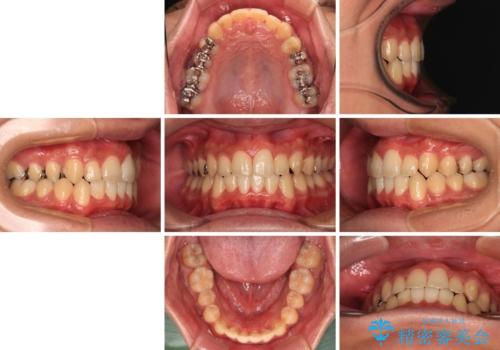

前歯のクロスバイト インビザラインによる矯正治療

- 上下のクロスバイトと前歯のデコボコを気にして来院された患者様です。

インビザラインを用い、IPR(歯と歯の間を削る)と歯列全体を拡大させることで、歯並びを整えていくこととしました。

インビザライン特有の、治療後半に奥歯が咬み合わないという事象が長引きました。

咬み合わないときの対処方法は色々とありますが、ゴムかけなどを活用して噛めるようにしました。